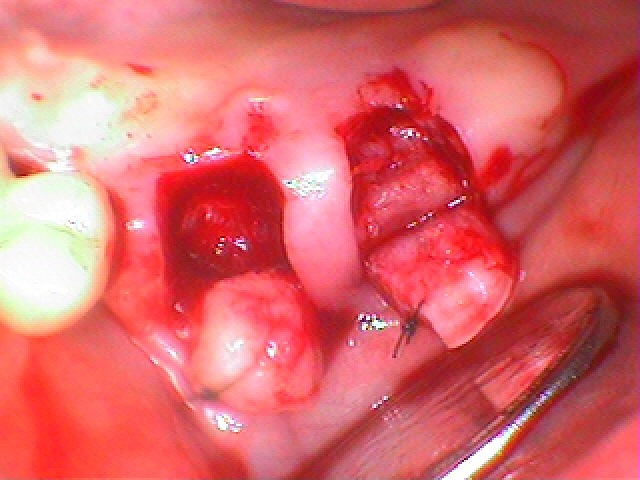

最小限で歯茎を開いてインプラントを埋入していきます

インプラント埋入時になります

6番は歯周病にて骨吸収がかなりの量であって深めにはなっています